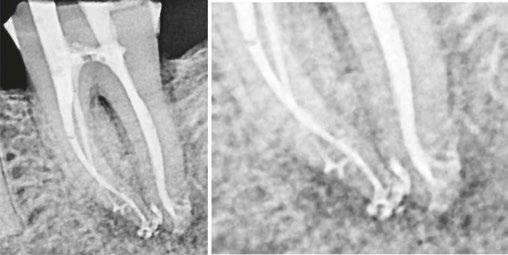

Figure 2 (left): PulpSucker Irrigation device with its stage, manifold, and supply lines feeding catheters placed to midroot in each canal, and its vacuum port exiting the top plate of the stage. Staging is a 3-minute procedure after which PulpSucker Irrigation runs by itself. Figure 3 (center): Preoperative radiography of this irreversibly inflammed mandibular molar shows incipient lucencies at both root apices and in the furcation between the roots. Figure 4 (right): PS cannulas in place 3 mm-5 mm short of the canal terminus

Figure 5 (left): The immediate post-op radiograph revealing a mid-root mesial canal exiting into the furcal lesion and a multiplicity of apical lateral canals in both roots. Figure 6 (center): Axial CBCT slice showing the mid-mesial canal filled into the center of the mid-root pathosis. Figure 7 (right): 3-month recall showing complete regeneration of periradicular bone adjacent to the lateral ports of exit

cord. Once the tooth is staged and catheterized, PulpSucker™ runs by itself (Figure 2).

Case report

Figures 3-7 show a lower molar treated with PulpSucker Irrigation after instrumenting the mesial canals to a 20-.03 shape and the distal canal to a 25-.05 shape. Obturation was accomplished with bioceramic sealer and the Continuous Wave filling technique.

Conclusion

Why are we so thrilled when we see lateral anatomy filled in our post-op radiography? It’s because 3D obturation of lateral recesses is a proxy for our irrigating efficacy. If you have not cleaned a lateral canal during irrigation procedures, you are not going to see it filled afterwards. Conversely, when several lateral canal projections are seen after treatment is finished, we can give ourselves a pat on the back for doing a thorough job of irrigation. This is no small accomplishment, especially in light of the recent trend toward minimally invasive endodontic procedures. In fact, MIE concepts and procedures up the ante of our mission to clean these uninstrumentable parts of root canals, and in fact, enhanced irrigation methods that produce cavitation have played a serious part in driving this trend (Figure 9). This case shows how really complex endodontic anatomy can

Figure 8: Close-up views of the apical two-thirds of the roots. The mid-mesial canal is 6 mm long; preoperatively, it contained vital pulp tissue, and it was never touched with a file, yet it has been definitively treated by PulpSucker Irrigation. Note the four lateral canals in the apical 2 mm of the roots, again, never touched by a file. Cavitation rocks

Figure 9: Mandibular molar treated with PulpSucker Irrigation through three independent MIE access openings. Note the apical delta system of lateral and accesssory canals in the apical third of the distal root. No dentin was cut in this canal by instruments, yet PulpSucker Irrigation was able to clear out the 5-7 portals of exit. This took 5 minutes to stage and catheterize, then ran by itself for the 15 minutes it took to run 100 mls of sodium hypochlorite through this super-complex root canal system

be effectively and automatically irrigated with a low cost, completely disposable PulpSucker device.